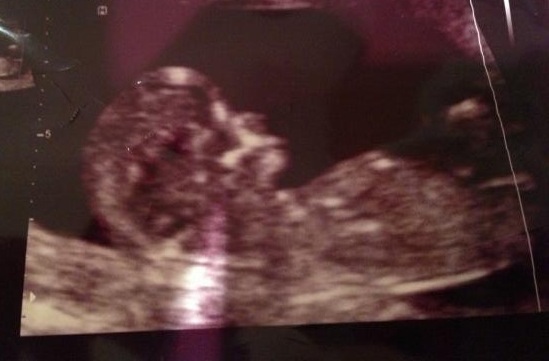

That's what I thought too, but does it look like there is a slight lift on the nub? I'm only on my phone so maybe I'm not seeing it clearly yet. Idk? My initial though is girl tho. Thanks!!

Looks super girly to me on my 20inch pc monitor ;)